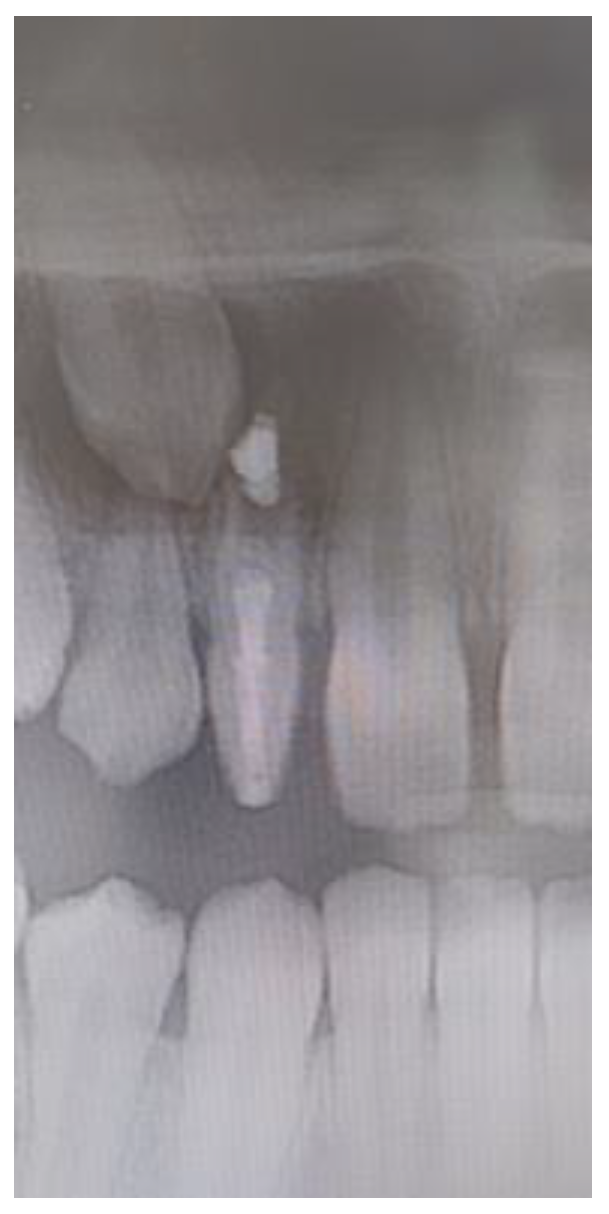

In the present study, talon cusp was found in five subjects (1.3%), on seven PMLI, without statistically significant differences between males and females and unilateral and bilateral side (p > 0.05). In all five (100%) subjects, talon cusp hindered the correct placement of the PMLI (Figure 4) and occlusion, so it was necessary to remove it. All seven talon cusps have an enamel layer covering a dentin without pulp; therefore, only removal of the tubercula and polishing of the surface was possible without endodontic treatment.

Figure 4. Talon cusp: (a) on the palatal surface of the permanent maxillary lateral incisor and (b) disturbed occlusion.